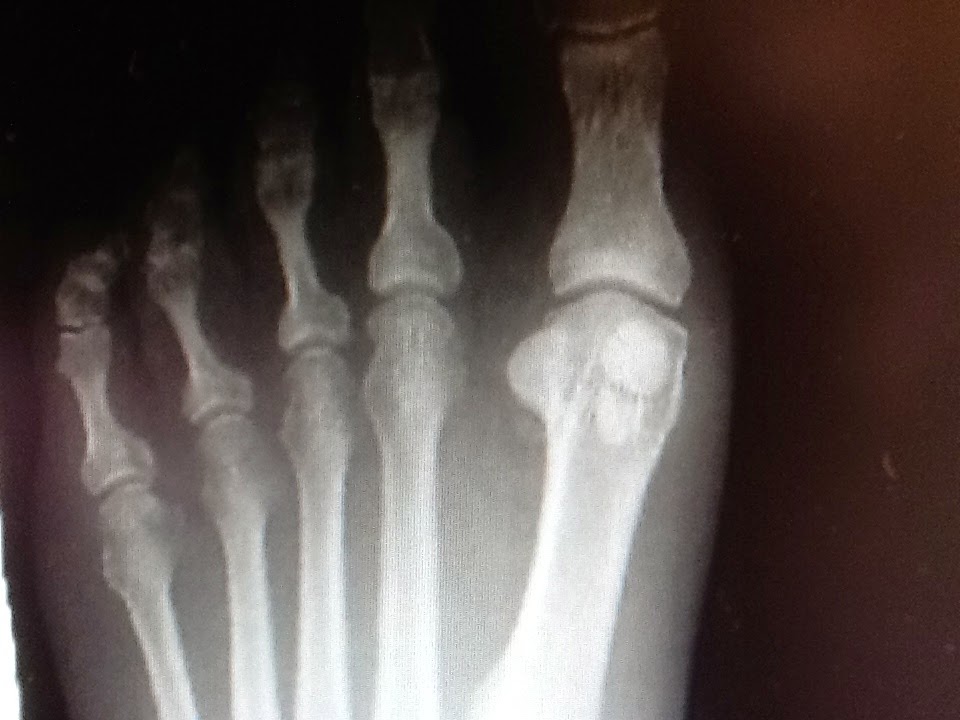

Because of their location, injuries to the sesamoid bones can be very difficult to treat. Sesamoid bones are located in the knees and feet. Sesamoid stress fractures are associated with localized tenderness over the involved sesamoid.

Seven months prior, she received a diagnosis of a medial sesamoid fracture. Journal of the american veterinary medical association. If surgery becomes necessary, several procedures are available to treat sesamoid problems. Sesamoids are found in several joints in the body. There are two methods for treating sesamoid problems, nonsurgical treatment and surgery. From injection therapy and orthotic care to surgical treatment options. A sesamoid is a bone embedded in a tendon. Sesamoid fractures occur as a result of trauma to a previous unipartite sesamoid bone. In other cases, if the sesamoids are fractured and does not heal correctly, removal of the sesamoids might be necessary. The most common cause of sesamoid fractures is from acute trauma to the foot, like if a person lands hard on their feet while running, jumping or falling. A sesamoid fracture that goes undiagnosed and untreated will invariably get worse. There can be inflammation of the tendons which are connected to the sesamoid (sesamoiditis) or there can be breakage of the sesamoid bone (sesamoid fracture). Seven months prior, she received a diagnosis of a medial sesamoid fracture. Pain will occur nearly immediately when a person fractures a sesamoid bone, but a person with sesamoiditis will experience pain gradually. Advanced treatments to rapidly heal sesamoid stress fractures. On some occasions, an acute fracture of unipartite sesamoid can be differentiated from a congenital bipartite. After the diagnosis from another physician, she did receive treatment, which included wearing a boot for five weeks.